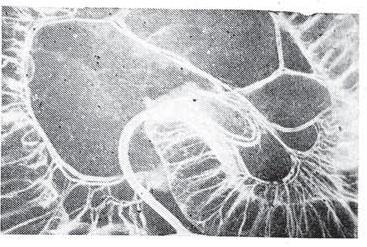

На рис. 3 представлена трансиллюмйнационная картина участка сигмовидной ободочной кишки после введения красителя в нижнюю брыжеечную артерию. У брыжеечного края кишки наряду с рисунком сосудов видно диффузное затенение (а), связанное с прокрашиванием пигментом тканей за пределами сосудов. Отсутствует изображение сопутствующих вен. Вместе с тем определяется четкий рисунок подслизистого артериального сплетения. В целом прямая артерия образует древовидный рисунок. От брыжеечного к противобрыжеечному краю происходит постепенное умень-калибРа ветвей с их многократным дихотомическим делением и анастомозиоо- кеНкишк113еТВЯМИ смежных ПРЯМЫ* артерий, расположенных на противоположной стен-

Рис. 3. Пигментная трансиллюминационная ангиограмма. Сигмовидная ободочная кишка. S. ш.— подслизистое артериальное сплетение, •а. е. — жировые подвески, а — диффузное затенение, связанное с прокрашиванием пигментом тканей за пределами сосудов.